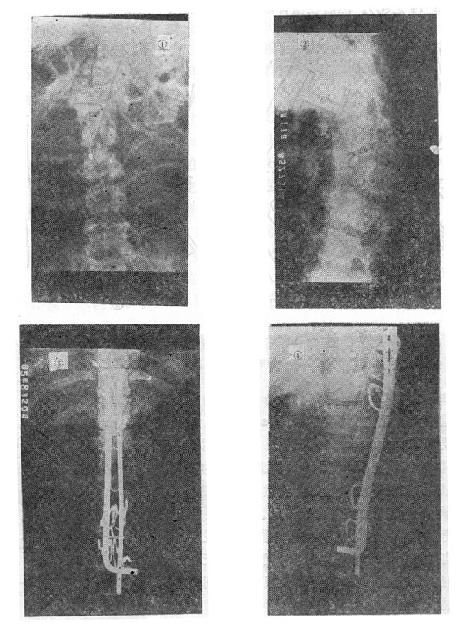

(三)爆裂型骨折的治疗 如不合并严重的神经系统症状,损伤又在两周以内者,可以用双Harrington法,撑开矫正,或用Dick手术;可以获得满意的结果(图73-13)。复位后需融合相邻两个椎间隙,因为CT常显示在爆裂型骨折中,相邻的上、下两个椎间盘均有损伤,如不融合,日后取棍后会出现腰痛。使用本法时,如前纵韧带完整,则很容易恢复椎体前方的高度。但爆裂型骨折存在下述三种情况时,需行前路减压术:①合并神经系统症状较重者;②就诊较晚,已两周以上者(常常10天以上就复位比较困难);③脊柱CT扫描显示已有较大的骨折片突出椎管内,使髓腔管变窄超过30%以上者,预示后纵韧带已有明显损伤,使用后路手术方法已无法使骨折片复位。Kostuik复习了日本和多伦多治疗脊柱骨折的结果后证实,前路减压术能使膀胱、肛门及肢体功能得到更好的恢复。

图73-13 爆裂型骨折的治疗 ①术前,骨折脱位;②术后,侧位;③术后,正位

(五)切片状骨折的治疗 因为这种骨折伴有整个韧带的完全撕裂,且常合并截瘫,用Harrington撑开棍治疗后方间隙反而会明显增宽。应选用强度较好的Luque或Dick装置为好,不仅能获得满意的复位(图73-16①~③),而且固定牢固,术后即可随意翻动病人,术后1-2即可让病人起床坐轮椅活动,有利于截瘫病人的康复与护理。

图73-16 切片骨折的治疗